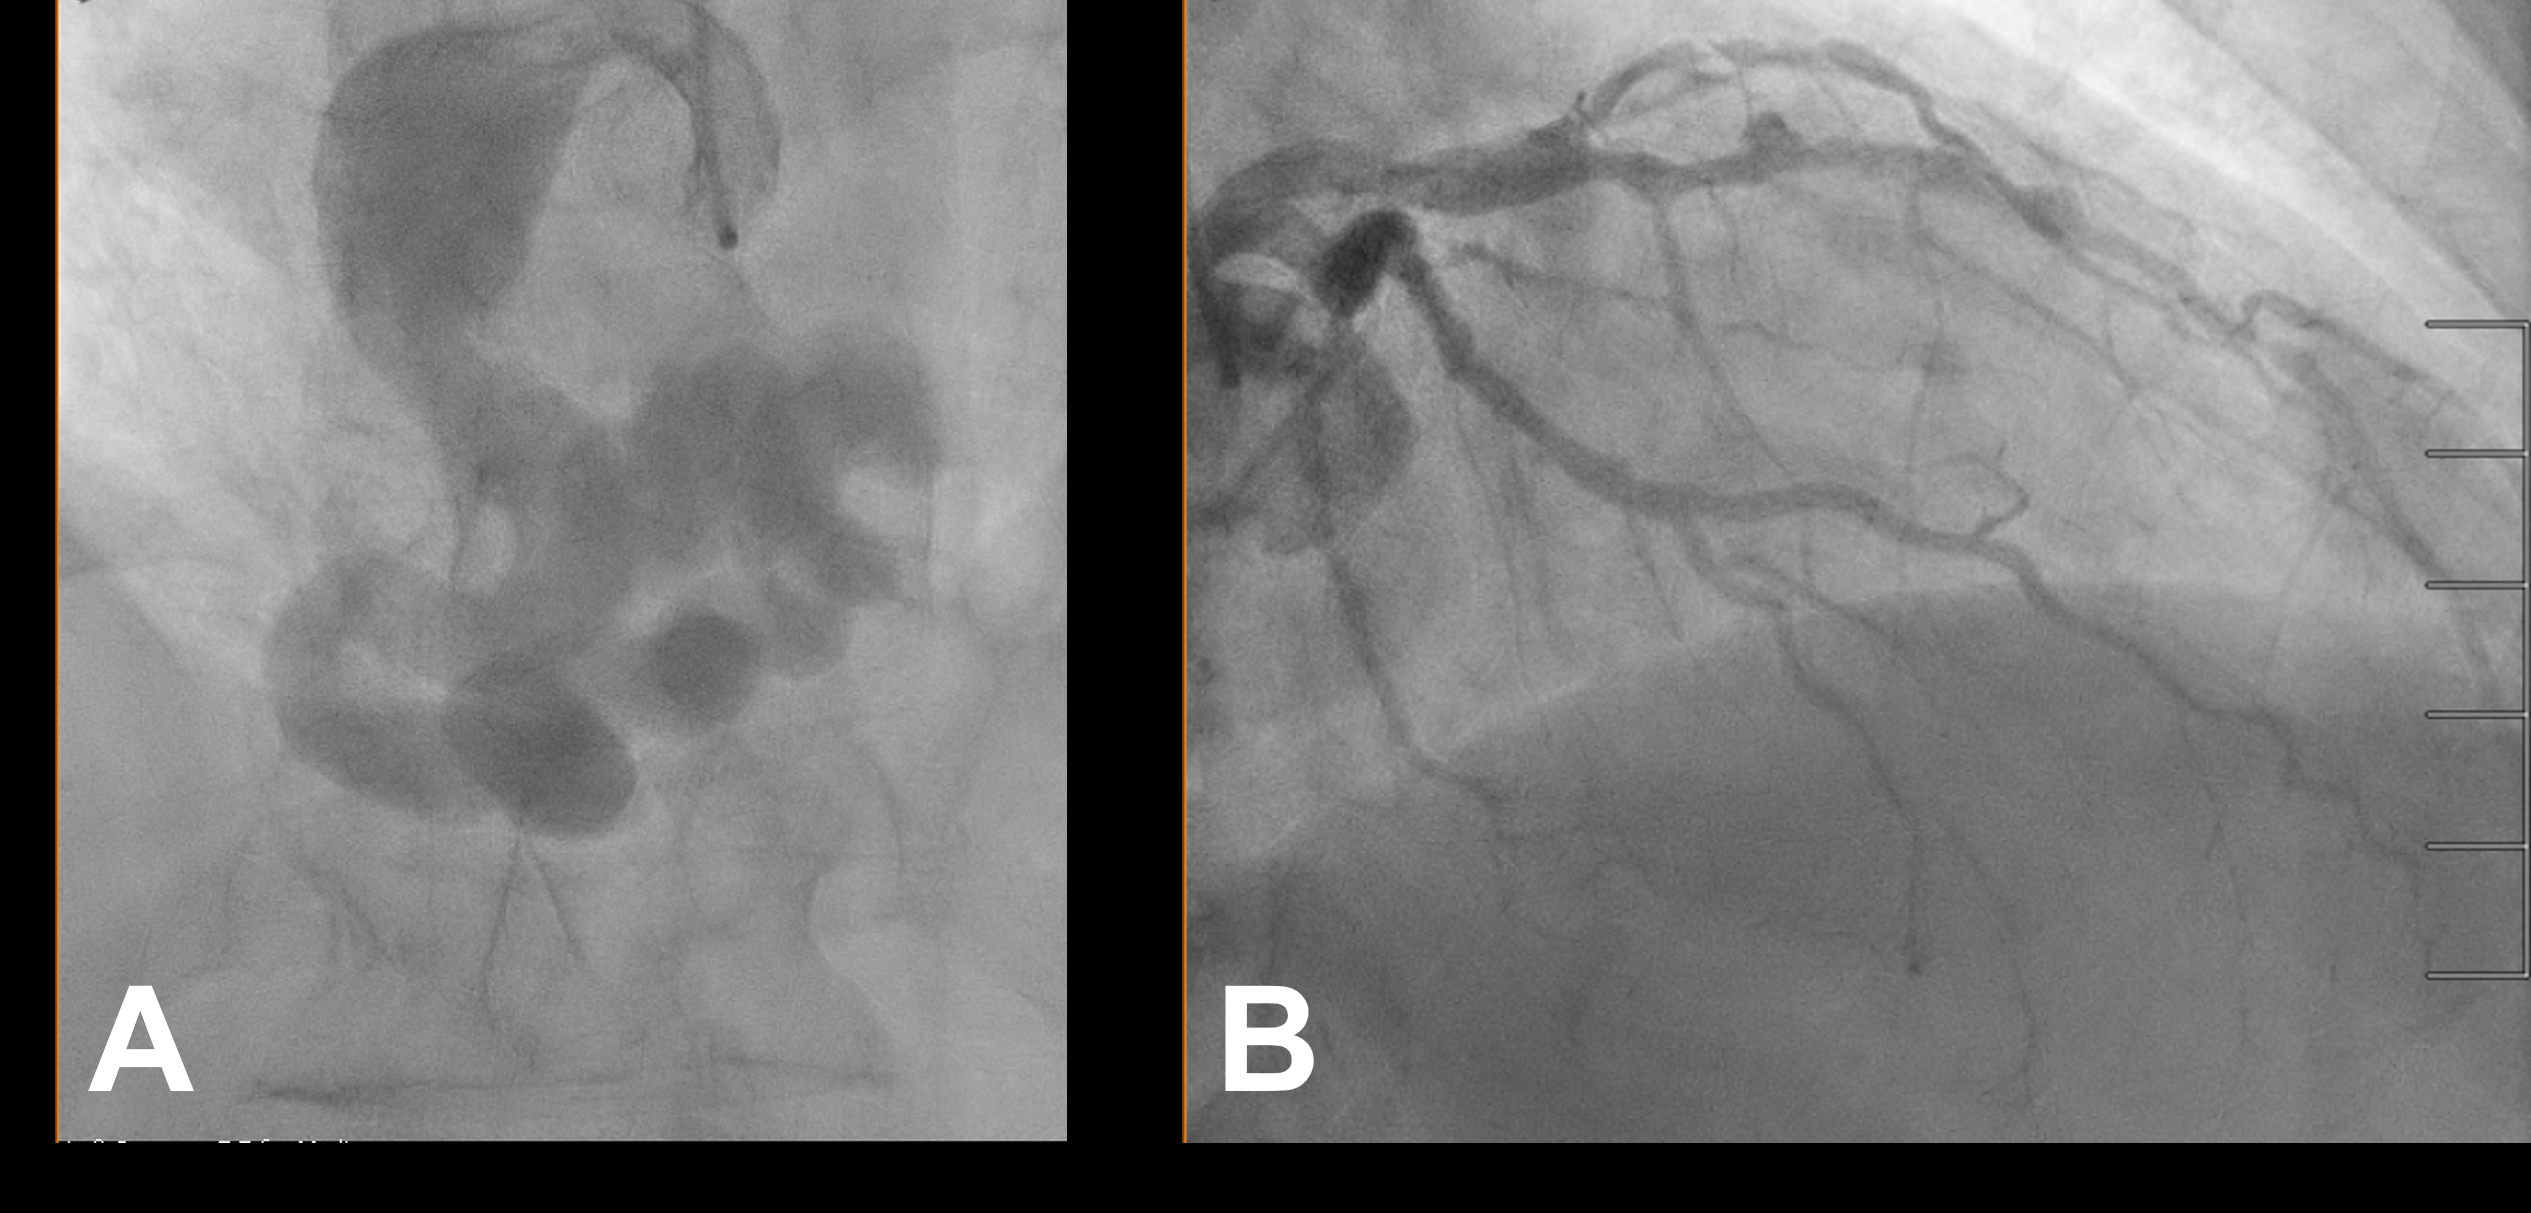

Echocardiography showed reduced LVEF of 30%, and cardiac catheterization found hemodynamically significant shunt with Qp:Qs of 1.47:1. Coronary angiography revealed a tortuous and extremely aneurysmal RCA, as well as multivessel coronary artery disease (mvCAD) involving LAD, D1, LCx, OM1. Notably, the LAD had multiple aneurysmal segments and areas of eccentric stenosis upto 90%.

Multislice CT angiography further characterized the RCA, which extends to the coronary sinus (CS) distally forming a coronary cameral fistula (CCF). Cardiac MRI did not show significant ischemic findings.